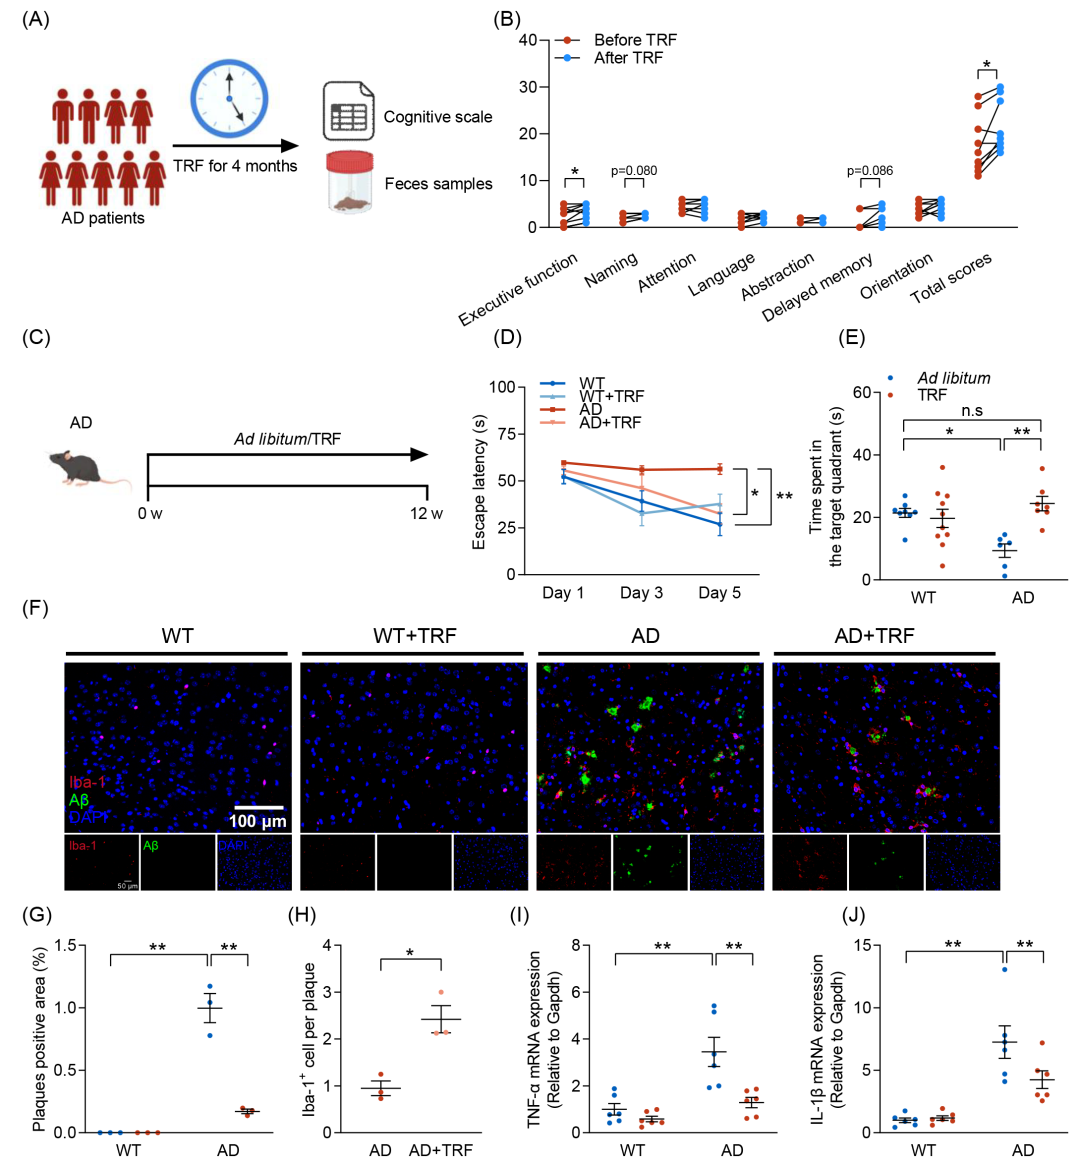

本研究综合运用海马转录组、粪便代谢组和肠道微生物组数据,从多层面挖掘证据,解析TRF依赖性改善AD认知障碍的微生物群-代谢物-脑轴机制。具体而言,我们对小鼠海马组织进行RNA测序,并将所有小鼠的183 Gb高质量RNA测序数据比对至小鼠(Mus musculus)基因组,共检测到10,272个基因,其中包括517个尚无注释的新预测基因。基因集富集分析(GSEA)揭示,在AD+TRF组中高表达的基因富集于多个生物学过程,包括IL-6信号通路、磷脂酸生物合成、线粒体调控及行为的正向调节(Benjamini-Hochberg校正后p < 0.01),而涉及神经系统发育、细胞过程的负调控及神经发生的基因则在TRF处理后呈现下调(p < 0.05)。进一步分析AD病理生理过程中重要的KEGG信号通路,如神经营养因子信号通路、mTOR信号通路、凋亡、AMPK信号通路及线粒体代谢(图2A),共筛选出381个基因用于偏最小二乘判别分析(PLSDA)。结果显示,AD组与AD+TRF组在PLSDA分析中可被明显区分(图2B),其中,电压门控钙通道亚基α1B(Cacna1b)、蛋白激酶C zeta(Prkcz)及环氧合酶-2(COX2)被鉴定为核心贡献因子,并在单变量分析中表现出显著的差异表达(图2C)。

随后,我们对粪便样本进行靶向代谢组学分析,以探究TRF处理对AD小鼠粪便代谢的影响,从而评估其对微生物活性的调节作用。共检测174种代谢物,包括氨基酸(n = 36)、苯甲酸类(n = 10)、胆汁酸(n = 32)、碳水化合物(n = 11)、肉碱类(n = 3)、脂肪酸(n = 32)、咪唑及吲哚类(n = 7)、有机酸(n = 24)、酚类及苯丙酸类(n = 10),以及短链脂肪酸(SCFAs,n = 9)(图2D及表S2)。结果显示,TRF显著增加了AD小鼠粪便中的胆汁酸(上升9.1%)及SCFAs(上升7.1%)总浓度,同时降低了脂肪酸(下降8.2%)及有机酸(下降6.7%)(图2D)。其中,TRF显著上调了咪唑丙酸(AD+TRF vs. AD,Fold change = 2.1, p = 0.04)及丙酸(PA)(AD+TRF vs. AD,Fold change = 1.5, p = 0.05)(图2E)。此外,TRF显著降低了牛磺去氧胆酸、3,4-二羟基氢桂皮酸、丙酰肉碱、异阿洛石胆酸、乳酸、木酮糖、核酮糖及硫酸化石胆酸的水平(图2E)。

鉴于肠道菌群在改善认知障碍中的关键作用,我们采用16S rRNA基因测序及全基因组鸟枪法宏基因组测序分析小鼠粪便样本,结果一致。TRF未能显著改变AD小鼠的肠道微生物群α-多样性、宏基因组功能通路丰度及功能变异性(图2F及图S3)。然而,TRF显著改变了肠道微生物组成,共检测到84种微生物分类单元在AD与AD+TRF组间呈现差异,其中36种在TRF干预后显著上调,48种显著下调(图S4A)。

进一步地,我们利用模糊C均值(Fuzzy C-means)聚类算法进行趋势聚类分析,以识别AD小鼠不同干预条件下的生物功能参数、AD病理相关差异表达基因、肠道菌群及粪便代谢物(变量数 = 6,372)的动态变化模式。最终确定16种不同的趋势聚类模式(图S4B)。其中,TRF在AD小鼠中上调的变量主要集中于Cluster 1、Cluster 4、Cluster 5、Cluster 14及Cluster 16,而下调的变量则聚集于Cluster 3、Cluster 8及Cluster 10。值得注意的是,大量与认知功能障碍及AD病理生理相关的TRF调控生物功能参数,与SCFAs(如PA)、特定胆汁酸及肠道菌群(Cluster 4及Cluster 16)呈现一致变化模式(图S4B)。其中,Akkermansia muciniphila与B. pseudolongum在AD小鼠中被TRF显著富集,且为丰度最高的菌种(图2G)。此外,TRF还增加了Bifidobacterium animalis及Bifidobacterium choerinum的相对丰度,尽管其水平低于B. pseudolongum(图2G,H)。进一步分析显示,TRF引起的生物功能参数变化、AD病理相关差异表达基因、肠道菌群及粪便代谢物之间存在密切的关联(图2I)。

综上,整合多组学分析表明,TRF通过调控肠道微生物群、微生物代谢物(如PA)及脑基因表达,构建了微生物群-代谢物-脑轴,从而介导TRF对AD小鼠认知功能障碍的改善作用。

图2. 综合多组学分析揭示了肠道微生物-代谢物-脑轴在TRF改善AD小鼠认知功能障碍中的作用机制

(A)基因本体(GO)分析显示通过基因集富集分析(GSEA)鉴定的关键基因,这些基因涉及AD的病理生理过程(n = 7-10);(B)采用偏最小二乘判别分析(PLSDA)对GSEA筛选出的关键AD病理生理相关基因进行分析,实现了AD+TRF组与AD组的显著区分;(C)PLSDA分析识别出的关键基因贡献者,可用于区分AD+TRF组和AD组;(D)归纳总结四组小鼠中10类主要代谢物的相对百分比;(E)AD+TRF组相较于AD组代谢物变化最显著的代谢物倍数变化;(F)功能富集分析显示AD+TRF组与AD组之间存在差异的肠道微生物功能通路;(G)AD+TRF组与AD组间显著变化的关键菌的相对丰度;(H)AD+TRF组相较于AD组变化最显著的肠道菌群倍数变化;(I)TRF调控的基因、代谢物、肠道微生物、生化参数与认知参数之间的相关性分析。